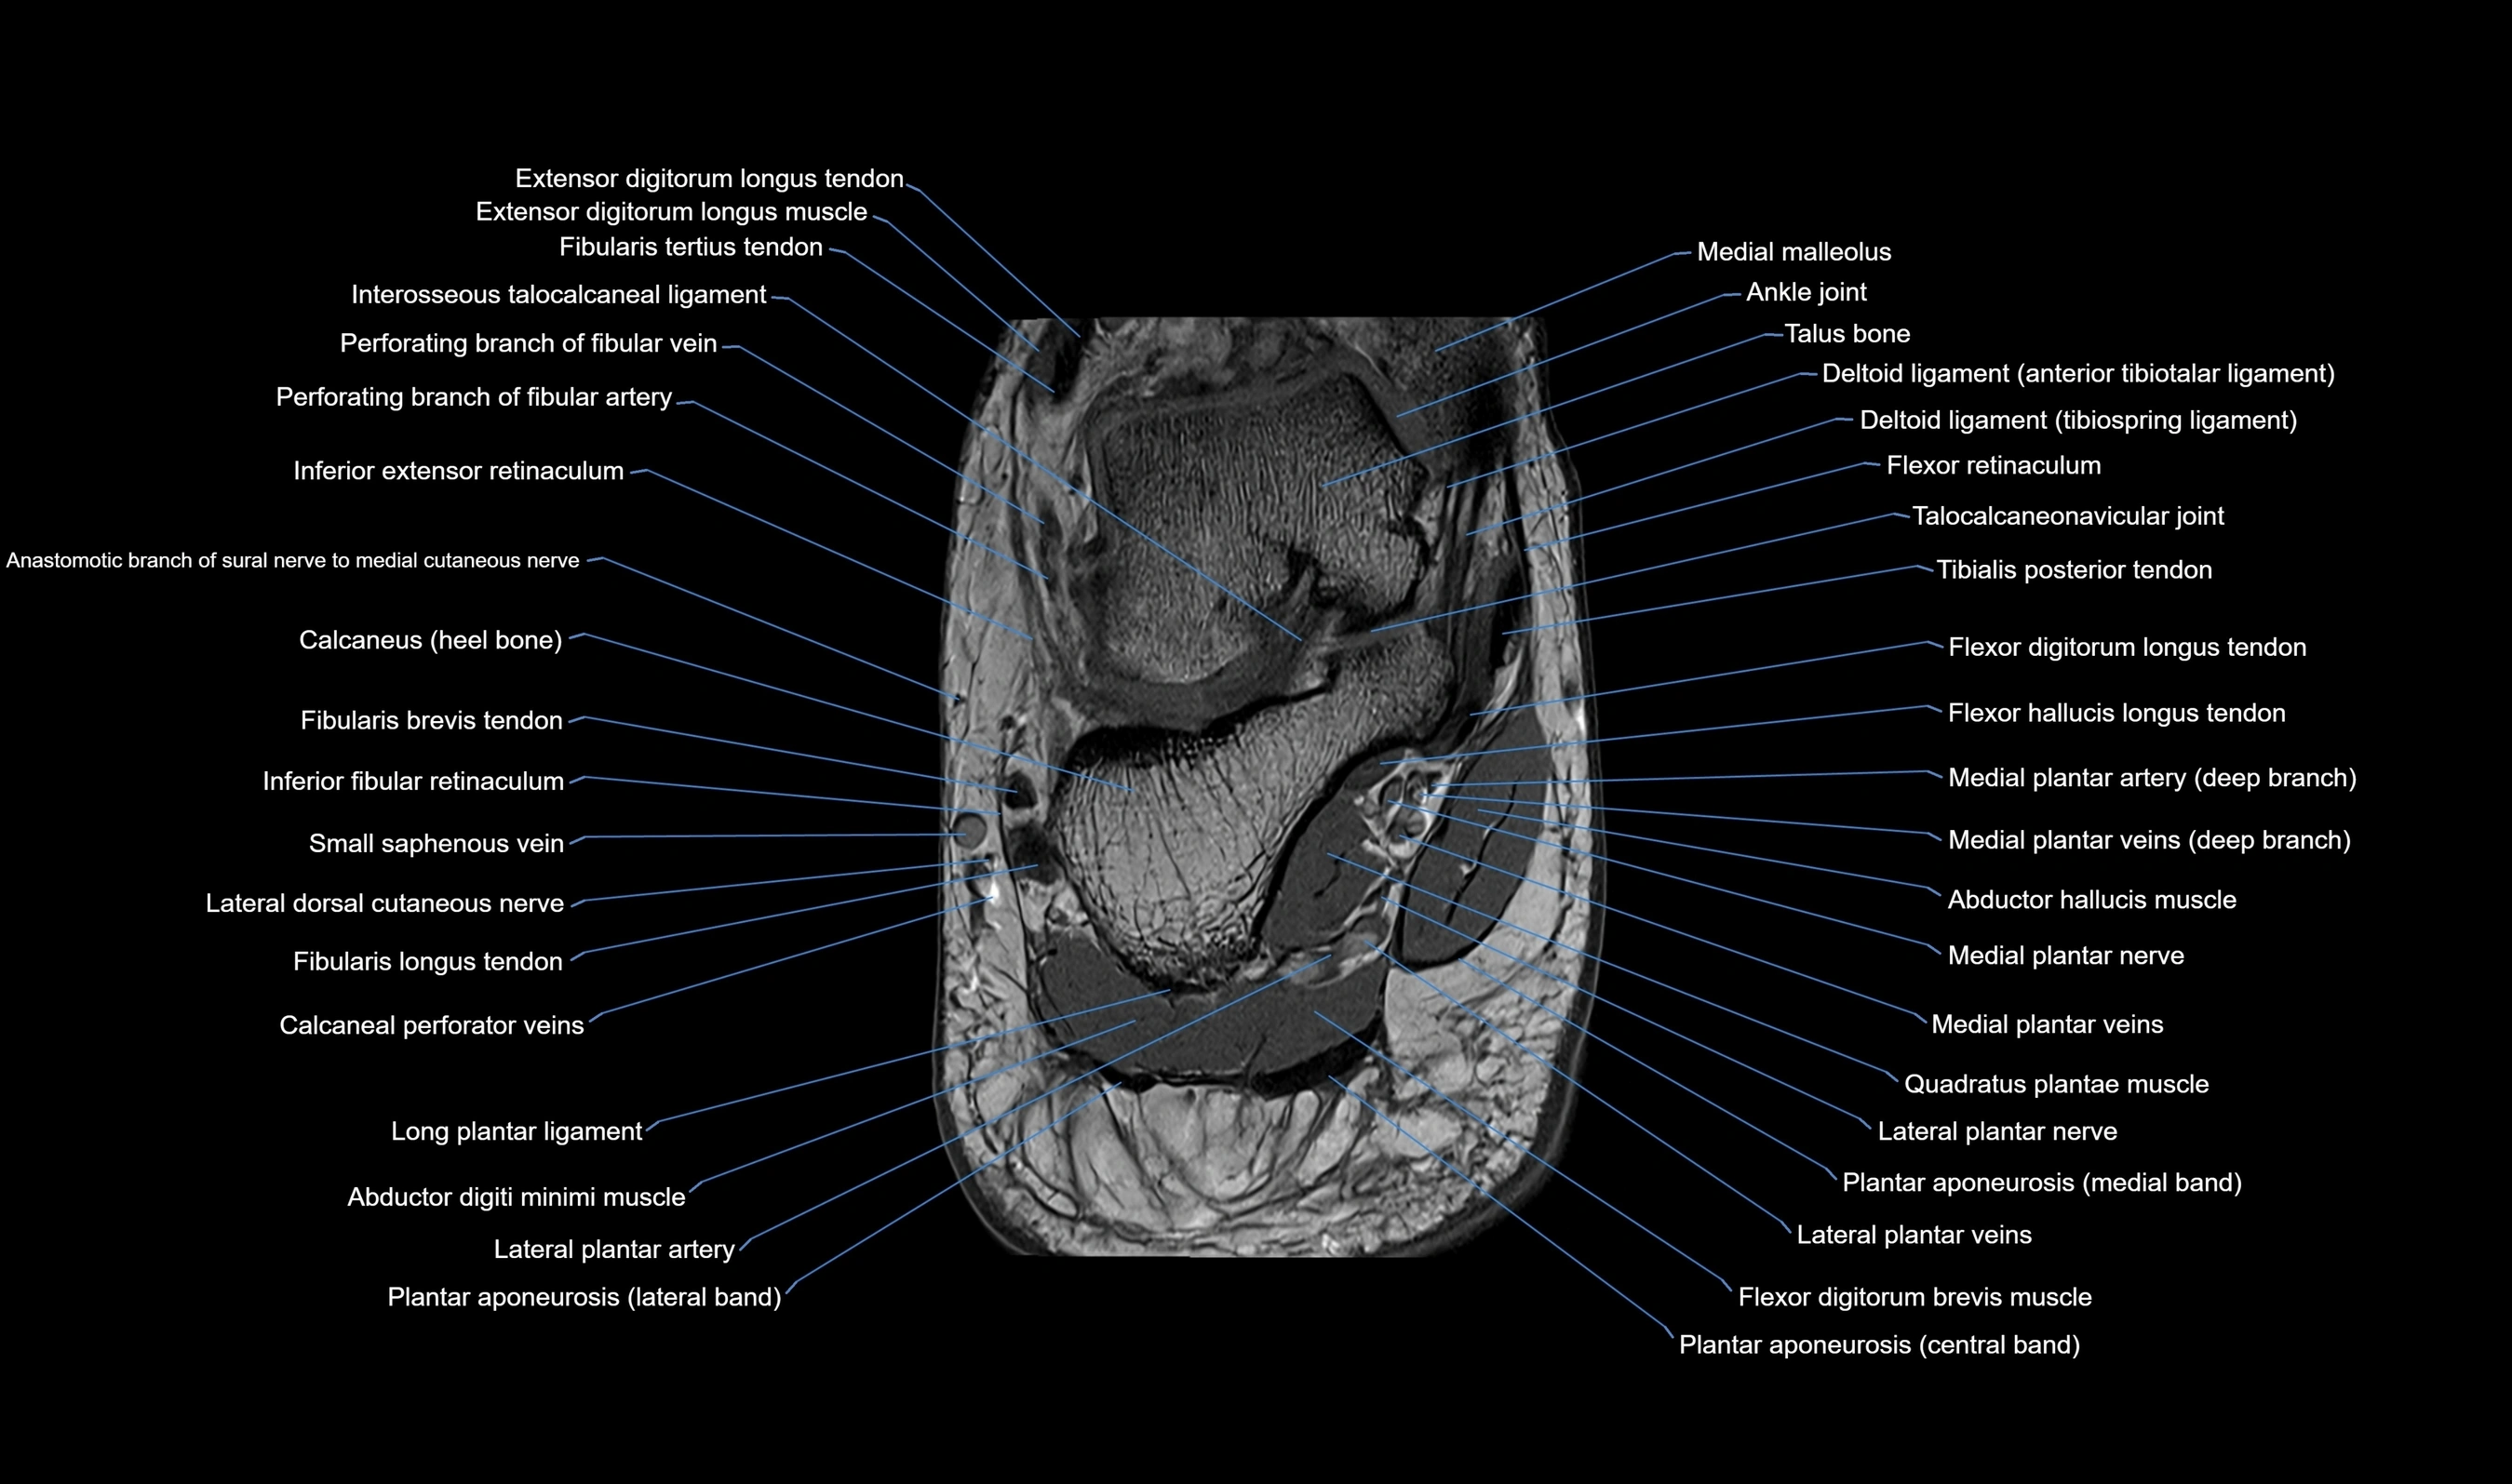

MRI image